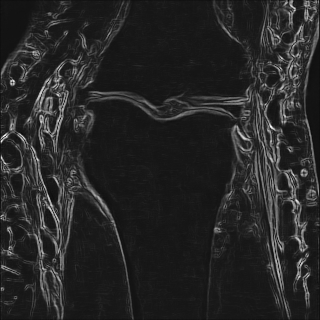

6.2.2 Quality of the Predicted Edges

EPN is utilized to provide edge priors for later reconstruction, so the quality of the predicted edges is very important. In Fig. 10, we provide some qualitative results of the predicted edges of EPN on three multi-coil datasets. Among them, the GT edges are extracted using the Sobel operator. As can be seen from the images, our proposed EPN can predict an approximate contour for the overall subject and can reconstruct accurate edges close to the GT edges under two acceleration factors. This fully verifies the effectiveness and excellence of the proposed EPN.

(a)

(b)

(c)

(d)